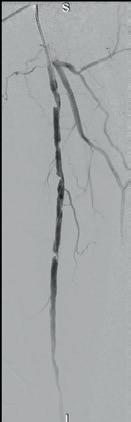

Shockwave E8 3mm x 80mm to the posterior tibial artery

The posterior tibial artery was successfully crossed first. The long-length posterior tibial artery disease was treated with a Shockwave E8 3.0mm x 80mm IVL catheter, with no pre-dilatation required. A total of 200 pulses were delivered along the length of the posterior tibial artery (Figure 3).

Shockwave E8 3mm x 80mm to the peroneal artery

Following this, the peroneal artery occlusion was successfully crossed. The longlength peroneal artery disease was treated with the same Shockwave E8 3mm x 80mm IVL catheter also with no pre-dilatation required. The remaining 200 pulses were

delivered across the length of the peroneal artery disease (Figure 3).